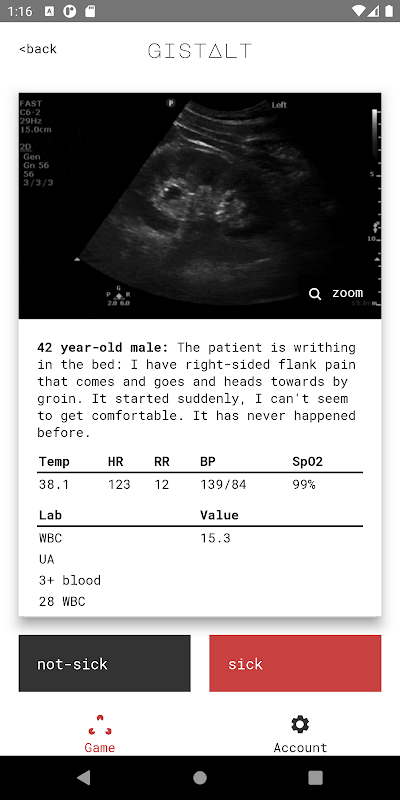

เป้าหมายของคุณในการเล่น Gistalt คือการระบุผู้ป่วยที่ป่วย (ต้องเข้ารับการรักษาในโรงพยาบาลหรือต้องเข้ารับการรักษาทันทีเพื่อให้อาการคงที่) หรือไม่ได้ป่วย (อาการที่สามารถรักษาได้อย่างปลอดภัยด้วยการติดตามผู้ป่วยนอก)

เกม Gistalt นั้นง่ายและสนุก คุณจะเริ่มต้นด้วยการนำเสนอผู้ป่วยหลายชุด ซึ่งรวมถึงสัญญาณชีพ ผลการตรวจทางห้องปฏิบัติการ และภาพ ปัดการ์ดแต่ละใบไปทางซ้าย (สำหรับไม่ป่วย) หรือขวา (สำหรับป่วย) เพื่อดูคำถามถัดไป เมื่อถึงท้ายชุด ให้ตรวจสอบคำตอบของคุณและดูคะแนนของคุณ คะแนน Gistalt ของคุณจะวัดความสามารถของคุณโดยเฉพาะในการตรวจจับผู้ป่วยที่อาการหนักที่สุดและกำหนดการรักษาที่จะสร้างความแตกต่าง